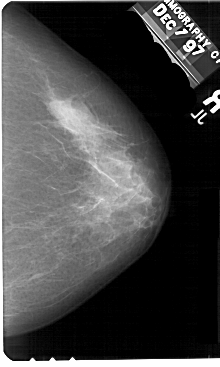

A_1584_1.LEFT_CC

LEFT_CC LINES 5491 PIXELS_PER_LINE 3376 BITS_PER_PIXEL 12 RESOLUTION 43.5 OVERLAY